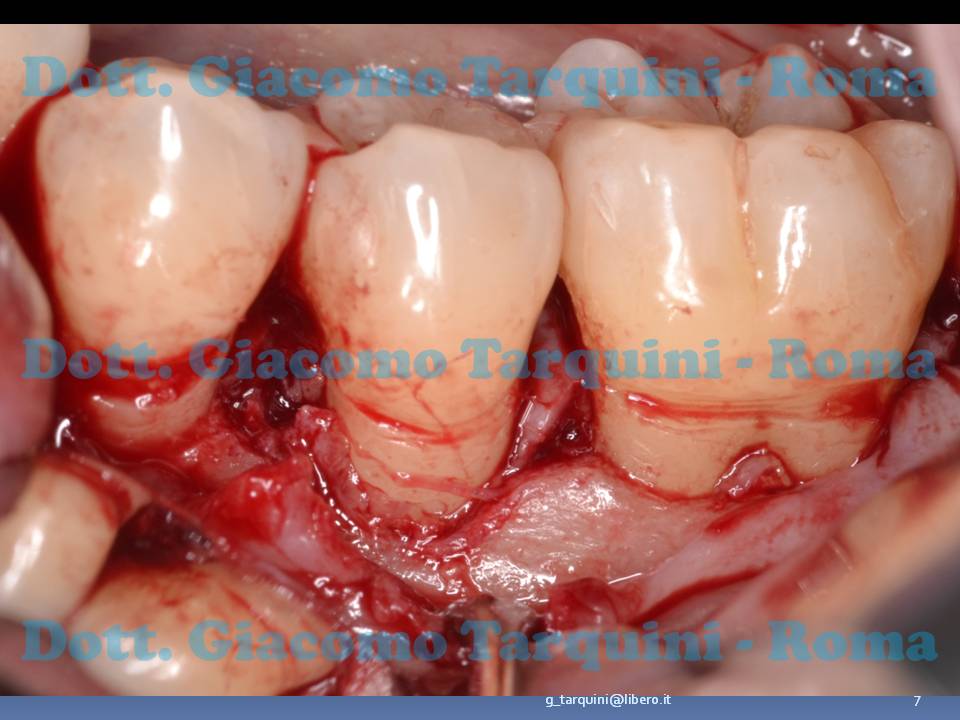

Il lembo viene scollato esponendo la sottostante cresta ossea

post-729-0-50532900-1500911964_thumb.jpg

La papilla interdentale tra 3.5 e 3.6 viene accuratamente sezionata e ribaltata sul versante linguale

post-729-0-45221300-1500911968_thumb.jpg

Particolare della preservazione di papilla

post-729-0-09322100-1500911973_thumb.jpg